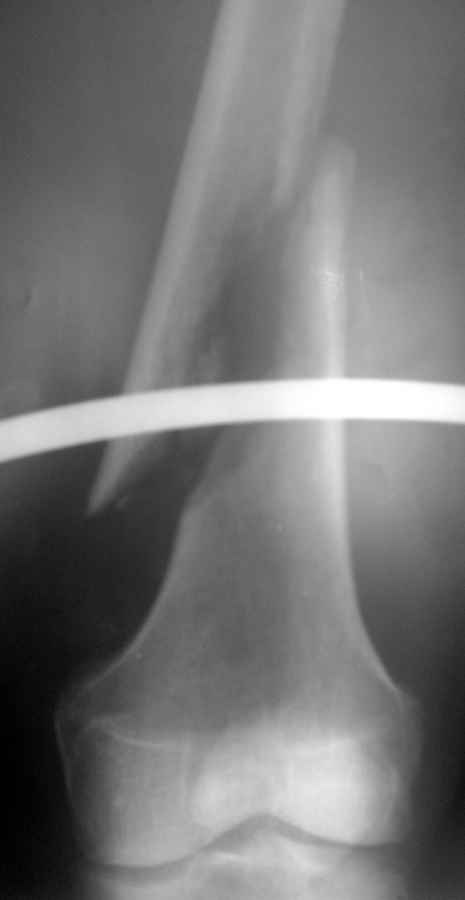

Доброго времени суток. 12.04.2011г. поступил пациент 64 лет, с косым переломом правой бедренной кости в нижней трети со смещением отломков. Из анамнеза: начали беспокоить боли в правом бедре, в течение месяца лечился амбулаторно (НПВП, физиолечение) - без эффекта, боли нарастали. 12.04.2011г. при ходьбе наступил патологический перелом бедра, "Скорой" доставлен в стационар. Rg-снимки в приложении. Клинически имеется припухлость в нижней трети, болезненная при пальпации. Опухоль? Обследуем. Больше ничего по онкопатологии нигде не нашли. Сегодня - подъем температуры до 39гр, бедро в области перелома на ощупь горячее, флюктуация по наружной поверхности. При пункции получен зловонный гной. Взяты посевы, анализ на цитологию, начато консервативное лечение острого гематогенного остеомиелита. Вопрос: а не может ли это быть опухолью?

По поводу оперативного лечения. У нас есть небольшой опыт консервативного лечения патологических переломов бедра при гематогенных остеомиелитах, с хорошими результатами. Видимо в этом случае пока продолжим консервативную тактику, но... Если оперировать... Какова может быть компоновка АВФв данном случае? Или интрамедуллярный спейсер с антибиотиком? И как его вводить? Через колено? Не хотелось бы. Да и промыванию канала бедра будет мешать. С ув. Кучерявый И.В.